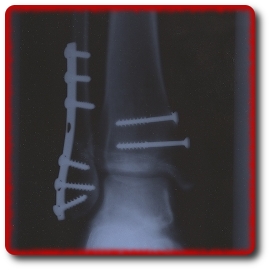

Ausbildung, Hausbau der Eltern und Verletzung